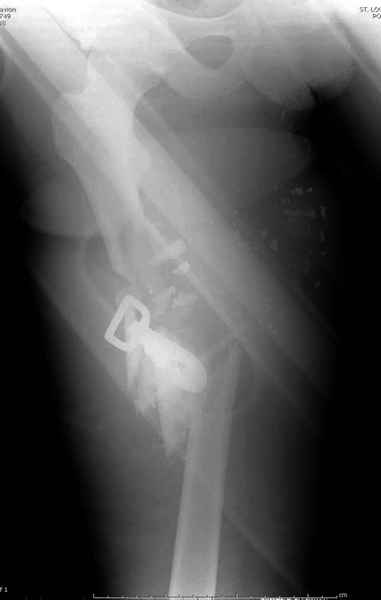

Здесь несколько примеров из нашей практики:

2 перелом бедра

На Вашем месте мы бы сделали ретроградний интрамедуллярный штифт. Нагрузка с первых дней не самоцель, хотя 12 мм штифт с двумя интерлокинг винтами выдерживает вес 75 кг., но разработку сустава можно начать как можно быстрее.